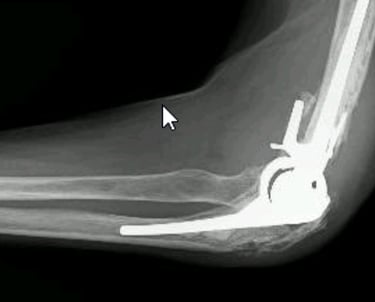

Coude

Soins adaptés pour les pathologies du coude, avec suivi personnalisé.